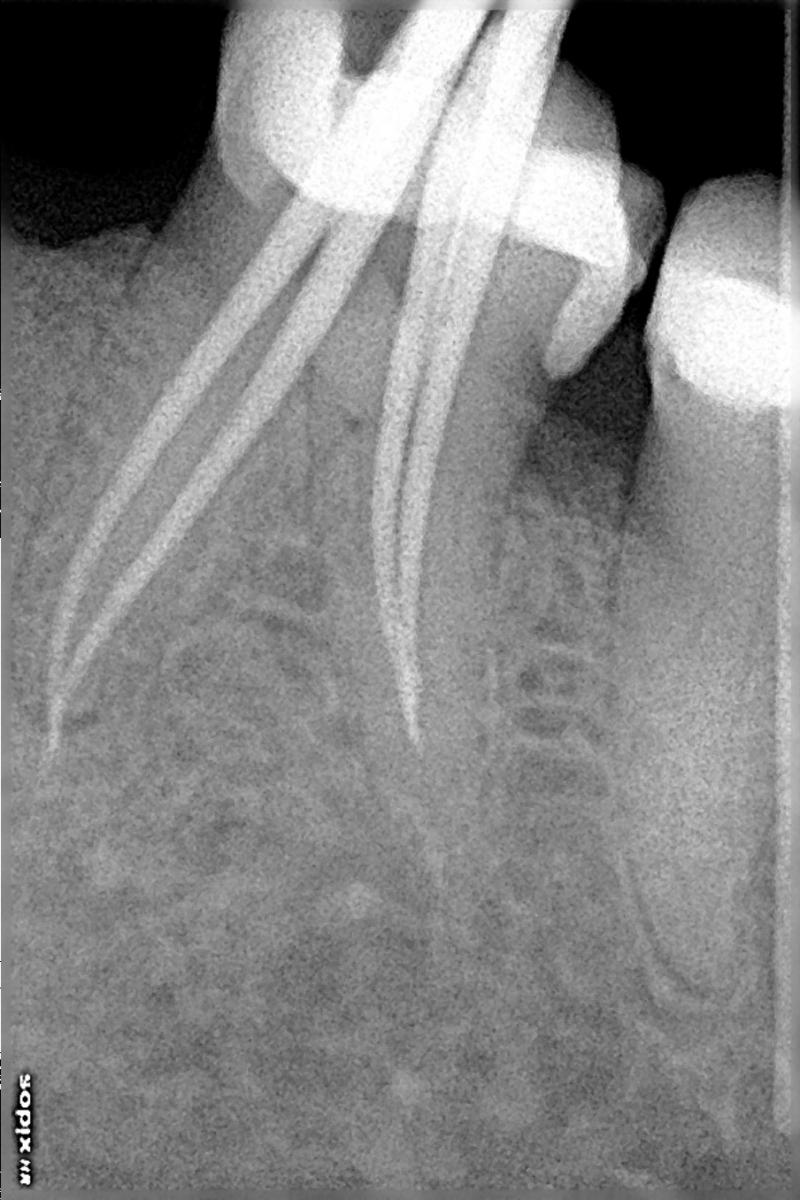

ROOT CANAL OF MOLAR TOOTH